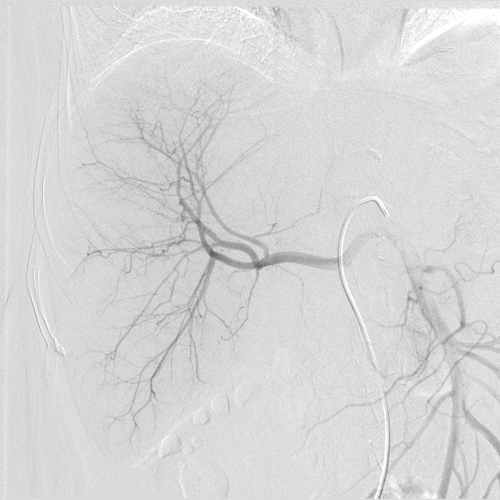

Селективная ангиография правой печеночной артерии в состоянии после эмболизации (симптом “обгорелого дерева”- конечная точка эмболизации)

21.03.2015г. больной И. А., у которой было злокачественное образование правой доли печени больших размеров, была проведена ангиография висцеральных артерий и селективная хемоэмболизация правой печеночной артерии с применением препаратoв Hepasphera 25 mg+Doxorubicin 100 mg.

П/о период протекал нормально, у больной наблюдался постэмболизационный синдром (считается нормальным в постоперационный период), который купировался медикаментозно.